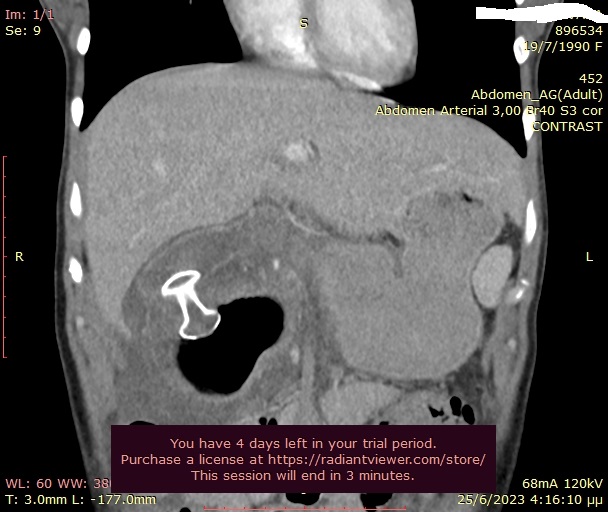

9) Παροχέτευση ψευδοκύστης παγκρέατος με την καθοδήγηση του ενδοσκοπικού υπερήχου και τοποθέτηση Hot Axios stent

Γυναίκα 33 ετών, με ιστορικό χειρουργικής παροχέτευσης ψευδοκύστης παγκρέατος προ 8ετίας, προσήλθε με κοιλιακό άλγος και εμέτους. Η αξονική τομογραφία κοιλίας έδειξε επανεμφάνιση μιας μεγάλης ψευδοκύστης με διάμετρο 11εκ στην περιοχή της παγκρεατικής κεφαλής, η οποία προκαλούσε πιεστικά φαινόμενα στο βολβό και τη 2η μοίρα του δωδεκαδακτύλου. Η κύστη περιείχε αρκετή ποσότητα υπερηχογενούς υλικού. Έγινε παροχέτευση της κύστης με τοποθέτηση LAMS (Hot Axios stent) 15x10χιλ από το δωδεκαδάκτυλο, με την καθοδήγηση του ενδοσκοπικού υπερήχου. Η όλη διαδικασία διήρκεσε 10 λεπτά και η ασθενής εξήλθε από την κλινική την επόμενη ημέρα. Σε επανέλεγχο μετά από 2 εβδομάδες η ψευδοκύστη είχε μικρύνει σε διάμετρο 3,3εκ. Το stent αφαιρέθηκε μετά από 5 συνολικά εβδομάδες χωρίς καμία επιπλοκή.

Ευμεγέθης ψευδοκύστη παγκρέατος

Υπερηχογραφική απεικόνιση του Hot Axios stent